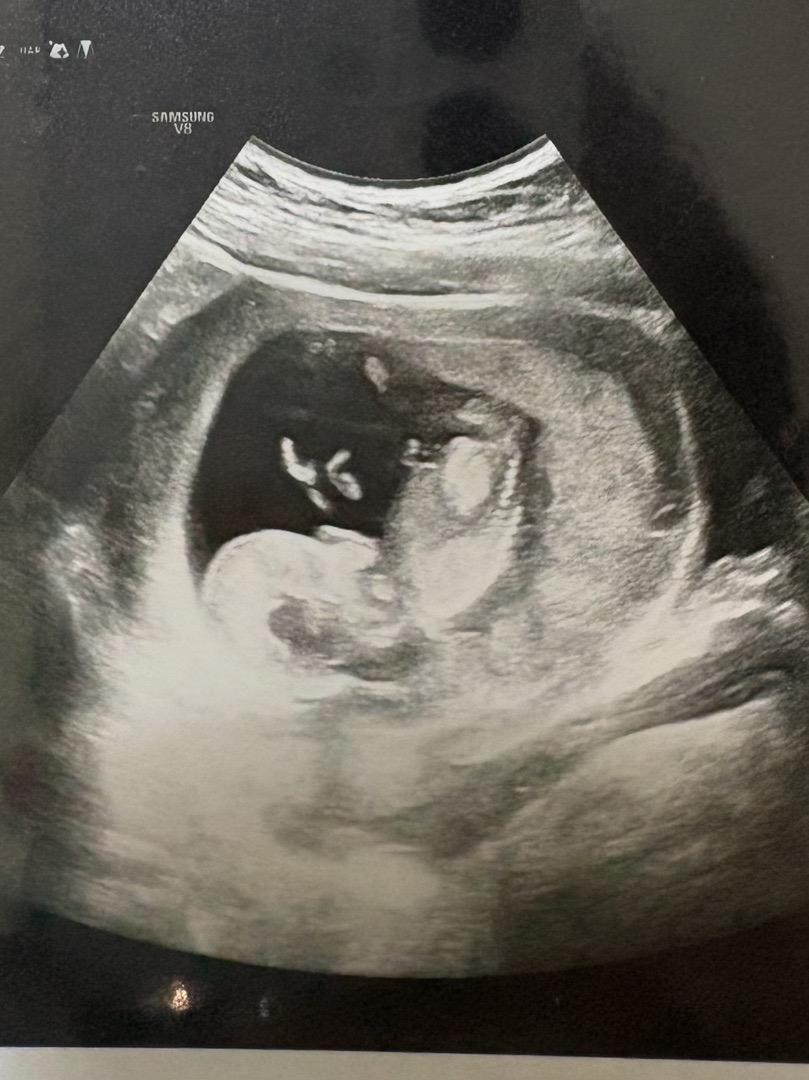

각도법 봐주세요 ㅠㅠ

각도법 봐주세요 ㅠㅠㅠ부탁드려요